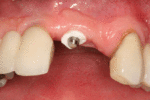

اذا كان العظم على استعداد لتلقي الزرع (أحيانا بعد سلسلة علاجات مسبقة)، يمكن البدء بعملية زرع الاسنان. يتم تثبيت المسامير المعدنية اللولبيه براغي، بعظم الفك. في سلسلة اخرى من العلاجات بعد فترة من ادخال البراغي، تبدا عمليات اعادة البناء عن طريق أخذ القياسات وانشاء التاج/الجسر. عندما يدور الحديث عن فترة الانتظار بين تركيب الغرسات وبين تنفيذ الاستبناء النهائي، فان هنالك اكثر من نهج واحد. النهج المتبع غالبا هو الانتظار لمدة 6 أسابيع على الأقل حتى تلتئم الانسجة، وأحيانا تصل فترة الانتظار لعدة شهور.

أول ستة أشهر

لا داعي لان يبقى المريض تحت المراقبة بعد عملية زراعة الاسنان . يجب عليه ان يتجنب الاكل او الشرب لمدة ساعتين بعد الجراحة، حتى ينتهي تاثير التخدير. قد يشعر بالم في المنطقة، وخصوصا في اليوم الاول بعد زرع الغرسات المعدنية، ويمكن استخدام المسكنات حسب الحاجة. قد تنتفخ منطقة دواعم السن لعدة ايام.

من اجل الحصول على النتائج الافضل بعد زرع الاسنان، يجب العناية بالاسنان وتنظيف الفم بشكل منتظم، بما في ذلك تنظيف الاسنان بواسطة فرشاة ناعمة (لمنع اصابة دواعم السن) والتنظيف بواسطة معدات خاصة. اذا كان هناك ارتفاع في درجة الحرارة، الم شديد، نزيف او افرازات موضعية من الفم، يجب التوجه للطبيب فورا.